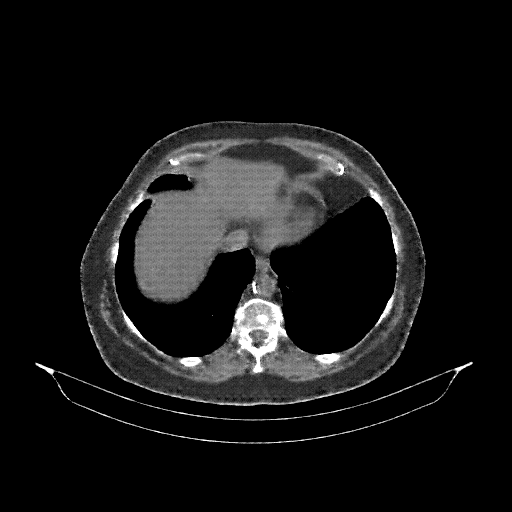

Slice 70 Targeting Evaluation

Slice: Slice_70

Slice Thickness: 3.0mm

Conversion: NATIVE β†’ VENOUS

Original NATIVE CT scan (input)

No window - Raw intensity values